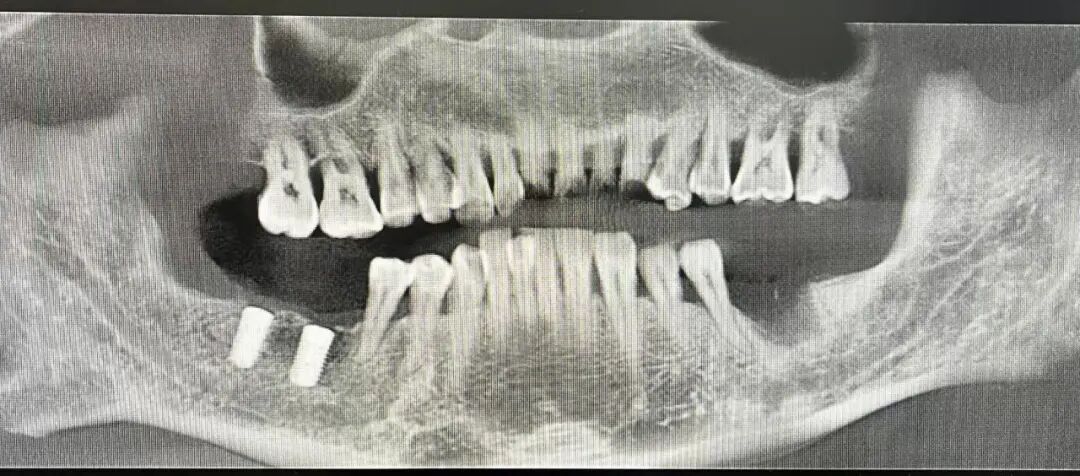

植牙焕新 重享口福

——种植牙技术成熟惠民生

十年磨一剑,科室种植牙技术历经多年打磨与实践,现已完全成熟开展,累计完成300例种植手术,成功实现隆阳人民拥有“第三副牙齿”的愿望。科室构建起从术前检查、方案设计,到种植手术、术后维护的全流程标准化诊疗体系,以精准的操作、规范的流程为缺牙患者提供安全高效的种植服务,有效解决老年患者缺牙咀嚼困难、中青年患者缺牙影响美观等问题,显著提升缺牙患者的生活质量。

种植前

种植后